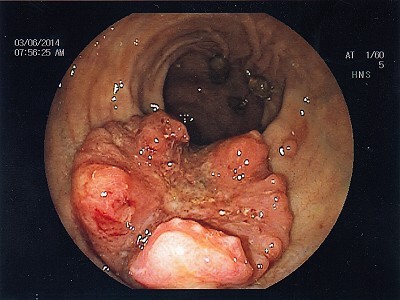

Abb. 1: Bösartiger Tumor des Übergangs von Mast- zu Dickdarm. Hier hilft ausschließlich eine Teilentfernung des Mast- und Dickdarmes. Abb. 1: Bösartiger Tumor des Übergangs von Mast- zu Dickdarm. Hier hilft ausschließlich eine Teilentfernung des Mast- und Dickdarmes.